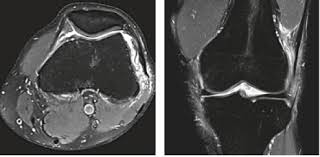

Soms wordt bij patiënten met het iliotibiale frictiesyndroom met behulp van MRI zelfs botoedeem. Dabei handelt es sich um eine Sehnenentzündung im Bereich des Knies. Gluteus maximus ogeller m.

Der Tractus iliotibialis verbindet Gesäß- und Hüfte mit dem Knie. De irritatie kan doordringen tot in het botweefsel. Ist eine Art großflächige Sehne die vom Beckenkamm über die Außenseite des Oberschenkels zieht und an der Außenseite des Schienbeinkopfes ansetzt.

Das Läuferknie oder Ilio-tibiales Bandsyndrom ITBS oder Tractussyndrom ist ein weitverbreitetes Schmerzsyndrom das durch Überbeanspruchung des Bewegungsapparates vor allem. Der Tractus iliotibialis ist eine Sehnenplatte und verläuft wie es der Namen schon verrät vom oberen vorderen Beckenrand seitlich entlang des Oberschenkels zum Schienbein. Het geïrriteerde weefsel betreft een dun laagje rijk gevasculariseerd en rijk geïnnerveerd vetweefsel. Bei ausreichender sportmedizinischer Erfahrung ist dies eine häufige und meist rein klinisch zu stellende Diagnose die keiner Röntgen- oder MRT-Aunahme bedarf. Ist eine Art großflächige Sehne die vom Beckenkamm über die Außenseite des Oberschenkels zieht und an der Außenseite des Schienbeinkopfes ansetzt. Gluteus maximus ogeller m. Das Läuferknie oder auch Tractus-iliotibialis-Syndrom ist eine Erkrankung die durch Überbelastung der Beine beim Sport entsteht. Soms wordt bij patiënten met het iliotibiale frictiesyndroom met behulp van MRI zelfs botoedeem. Schmerzen können hierbei im gesamten Verlauf vorkommen.